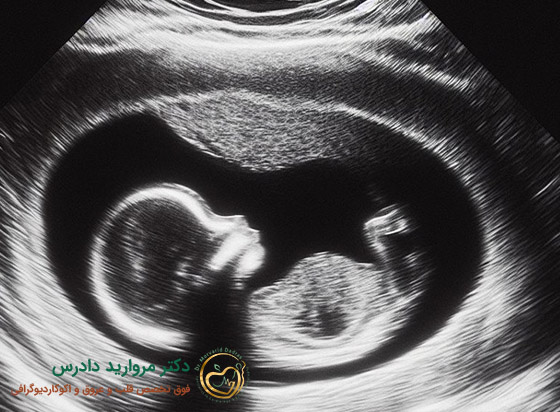

اکو سه بعدی جنین یکی از مهم ترین روش های بررسی ناهنجاری های قلبی مادرزادی است. این آزمایش معمولاً بین هفته های ۱۸ تا ۲۴ بارداری انجام می شود و به پزشک کمک می کند ساختار و عملکرد قلب نوزاد را قبل از تولد بررسی کند. این روش برای مادرانی توصیه می شود که:

بله، این روش بین هفته های ۱۸ تا ۲۴ بارداری برای بررسی ناهنجاری های مادرزادی قلب جنین بسیار کاربرد دارد.